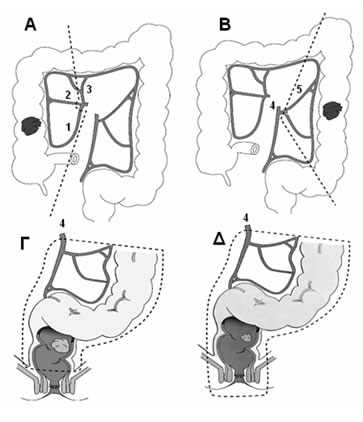

Επιλογή χειρουργικής επέμβασης

Καρκίνωμα τυφλού ή ανιόντος κόλου:

- Διενεργείται δεξιά κολεκτομή.

- Απολινώνονται η ειλεοκολική, η δεξιά κολική αρτηρία και ο δεξιός κλάδος της μέσης κολικής αρτηρίας και, μετά την αφαίρεση του δεξιού κόλου, αποκαθίσταται η εντερική συνέχεια με ειλεο-εγκαρσία αναστόμωση (Εικόνα 12).

Καρκίνωμα εγκαρσίου κόλου:

- Για όγκους της ηπατικής καμπής διενεργείται δεξιά κολεκτομή.

- Για όγκους του εγκαρσίου διενεργείται δεξιά εκτεταμένη κολεκτομή, κατά την οποία, εκτός των αγγείων του δεξιού κόλου, απολινώνεται η μέση κολική αρτηρία και, μετά την αφαίρεση του δεξιού και του εγκαρσίου κόλου, εκτελείται ειλεο-κολική αναστόμωση με το κατιόν κόλον (Εικόνα 13).

- Ο καρκίνος της σπληνικής καμπής μπορεί να εμφανίσει λεμφαδενική διασπορά στους λεμφαδένες κατά μήκος της μέσης κολικής ή της αριστερής κολικής αρτηρίας. Έτσι, μία πιο ριζική κολεκτομή με συναφαίρεση του κατιόντος κόλου διενεργείται (υφολική κολεκτομή), ενώ η συνέχεια αποκαθίσταται με την εκτέλεση ειλεο-σιγμοειδικής αναστόμωσης.

Καρκίνωμα κατιόντος κόλου:

- Διενεργείται αριστερή κολεκτομή, με την απολίνωση της κάτω μεσεντερίου ή των κλάδων της (αριστερή κολική και σιγμοειδικές αρτηρίες) και αναστομώνεται η μεσότητα του εγκαρσίου με το ανώτερο ορθό (Εικόνα 12).

Καρκίνωμα σιγμοειδούς:

- Διενεργείται σιγμοειδεκτομή με την απολίνωση της κάτω μεσεντερίου μετά την έκφυση της αριστερής κολικής (προκειμένου η τελευταία να διατηρηθεί) και αναστομώνεται το κατιόν κόλον με το ανώτερο ορθό.

- Σε καρκίνωμα του αριστερού κόλου με απόφραξη ή διάτρηση διενεργείται ογκολογική εκτομή του πάσχοντος τμήματος και τελική κολοστομία χωρίς αναστόμωση (επέμβαση κατά Hartmann) ή, ειδικά εάν η απόφραξη έχει οδηγήσει σε εκσεσημασμένη διάταση με ισχαιμία ή και διάτρηση του τυφλού, διενεργείται υφολική κολεκτομή (Εικόνα 14).

Εικόνα 12.

Τύποι χειρουργικών επεμβάσεων για την αντιμετώπιση του ορθοκολικού καρκίνου.

Α. Δεξιά κολεκτομή. Β. Αριστερή κολεκτομή. Γ. Χαμηλή πρόσθια εκτομή. Δ. Κοιλιοπερινεϊκή εκτομή

(1: ειλεοκολική αρτηρία, 2: δεξιά κολική αρτηρία, 3: μέση κολική αρτηρία, 4: κάτω μεσεντέριος αρτηρία, 5: αριστερή κολική αρτηρία)